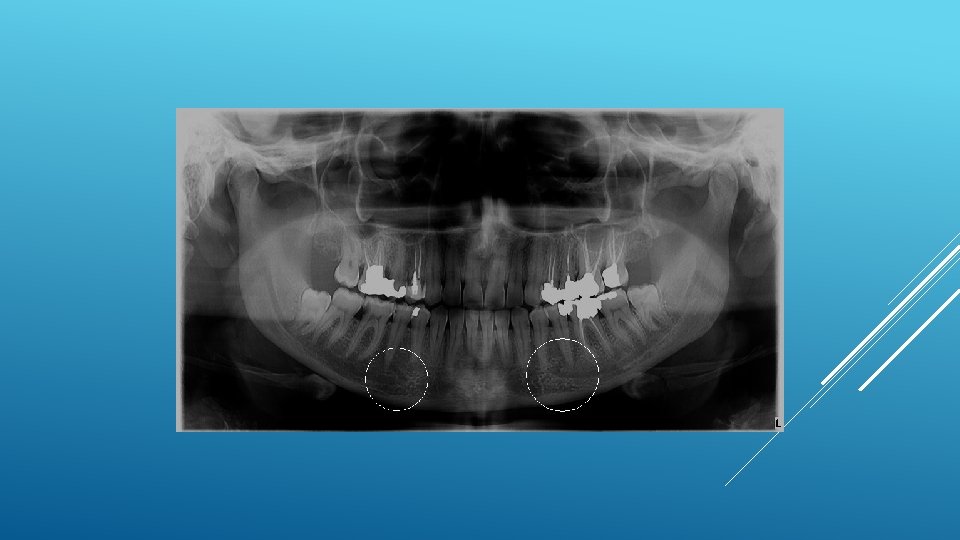

LOCATION AND DIMENSIONS OF THE MENTAL FORAMEN: A RADIOGRAPHIC ANALYSIS BY USING CONE-BEAM COMPUTED TOMOGRAPHY The majority of MF (56%) were located apically between the 2 premolars, and another 35. 7% of MF were positioned below the second premolar. On average, the MF was localized 5. 0 mm from the closest root of the adjacent tooth (range, 0. 3 -9. 8 mm). The mean size of the MF showed a height of 3. 0 mm and a length of 3. 2 mm; however, individual cases showed large differences in height (1. 8 -5. 1 mm) and in length (1. 8 -5. 5 mm). All mental canals exiting the MF demonstrated an upward course in the coronal plane, with 70. 1% of the mental canal presenting an anterior loop (AL) in the axial view. The mean extension of AL in cases with an AL was 2. 3 mm.

RELATIONSHIP BETWEEN THE POSITION OF THE MENTAL FORAMEN AND THE ANTERIOR LOOP OF THE INFERIOR ALVEOLAR NERVE AS DETERMINED BY CONE BEAM COMPUTED TOMOGRAPHY COMBINED WITH MIMICS The parameters were measured, and their values include mean (SD) anterior loop length, 1. 16 (1. 78) mm; anterior loop angle, 19. 13 (26. 89) degrees; inferior alveolar canal diameter, 3. 01 (0. 67) mm; height of the inferior alveolar canal, 10. 32 (1. 56) mm; 2 -dimensional mental foramen diameter, 2. 97 (0. 61) mm; 3 D mental foramen diameter, 2. 95 (0. 59) mm; 2 -dimensional vertical height of the mental foramen, 14. 67 (1. 67) mm; and 3 D vertical height of the mental foramen, 14. 61 (1. 69) mm. The mental foramen was located apically between the first and second premolars in 51. 67% and below the second premolar in 40. 83% of the cases.

THE MENTAL FORAMEN OR "THE CROSSROADS OF THE MANDIBLE. " AN ANATOMIC AND CLINICAL OBSERVATION] [ARTICLE IN FRENCH, GERMAN] THOMAS VON ARX 1 This paper presents a clinical and anatomical review of the mental foramen (MF) based on recent publications (since 1990). Usually, the MF is located below the 2 nd premolar or between the two premolars, but it may also be positioned below the 1 st premolar or below the mesial root of the 1 st molar. At the level of the MF, lingual canals may join the mandibular canal (hence the term "crossroads"). Accessory MF are frequently described in the literature with large ethnic variations in incidence. The emergence pattern of the mental canal usually has an upward and posterior direction. The presence and extent of an "anterior loop" of the mental canal may be overestimated with panoramic radiography. Limited cone-beam computed tomography currently appears to be the most precise radiographic technique for assessment of the "anterior loop". The mental nerve exiting the MF usually has three to four branches for innervation of the soft tissues of the chin, lower lip, facial gingiva and mucosa in the anterior mandible. The clinician is advised to observe a safety distance when performing incisions and osteotomies in the vicinity of the MF.

ANATOMICAL RELATIONSHIP BETWEEN MENTAL FORAMEN, MANDIBULAR TEETH AND RISK OF NERVE INJURY WITH ENDODONTIC TREATMENT he root apex of the mandibular second premolar (70 %), followed by the first premolar (18 %) and then the first molar (12 %), was the closest to the MF. Ninetysix percent of root apices evaluated were >3 mm from the MF. An AL was present in 88 % of the cases. Conclusions: With regards to endodontic treatment, the risk of nerve injury in the vicinity of the MF would appear to be low. However, the high incidence of the AL highlights the need for clinicians to be aware and careful of this important anatomical feature.

ASSESSMENT OF MORPHOLOGICAL AND ANATOMICAL CHARACTERISTICS OF MENTAL FORAMEN USING CONE BEAM COMPUTED TOMOGRAPHY All mental foramina were visualized. Regarding location, 49. 2% of the MFs were located between first and second premolars, 7. 7 distal and 39. 7% coincident to the apex of the mandibular second premolar. The mean MF opening angle was 45. 4° on the right side, and 45. 9° on the left. There were no statistically differences between gender groups with regard to the opening angle degree